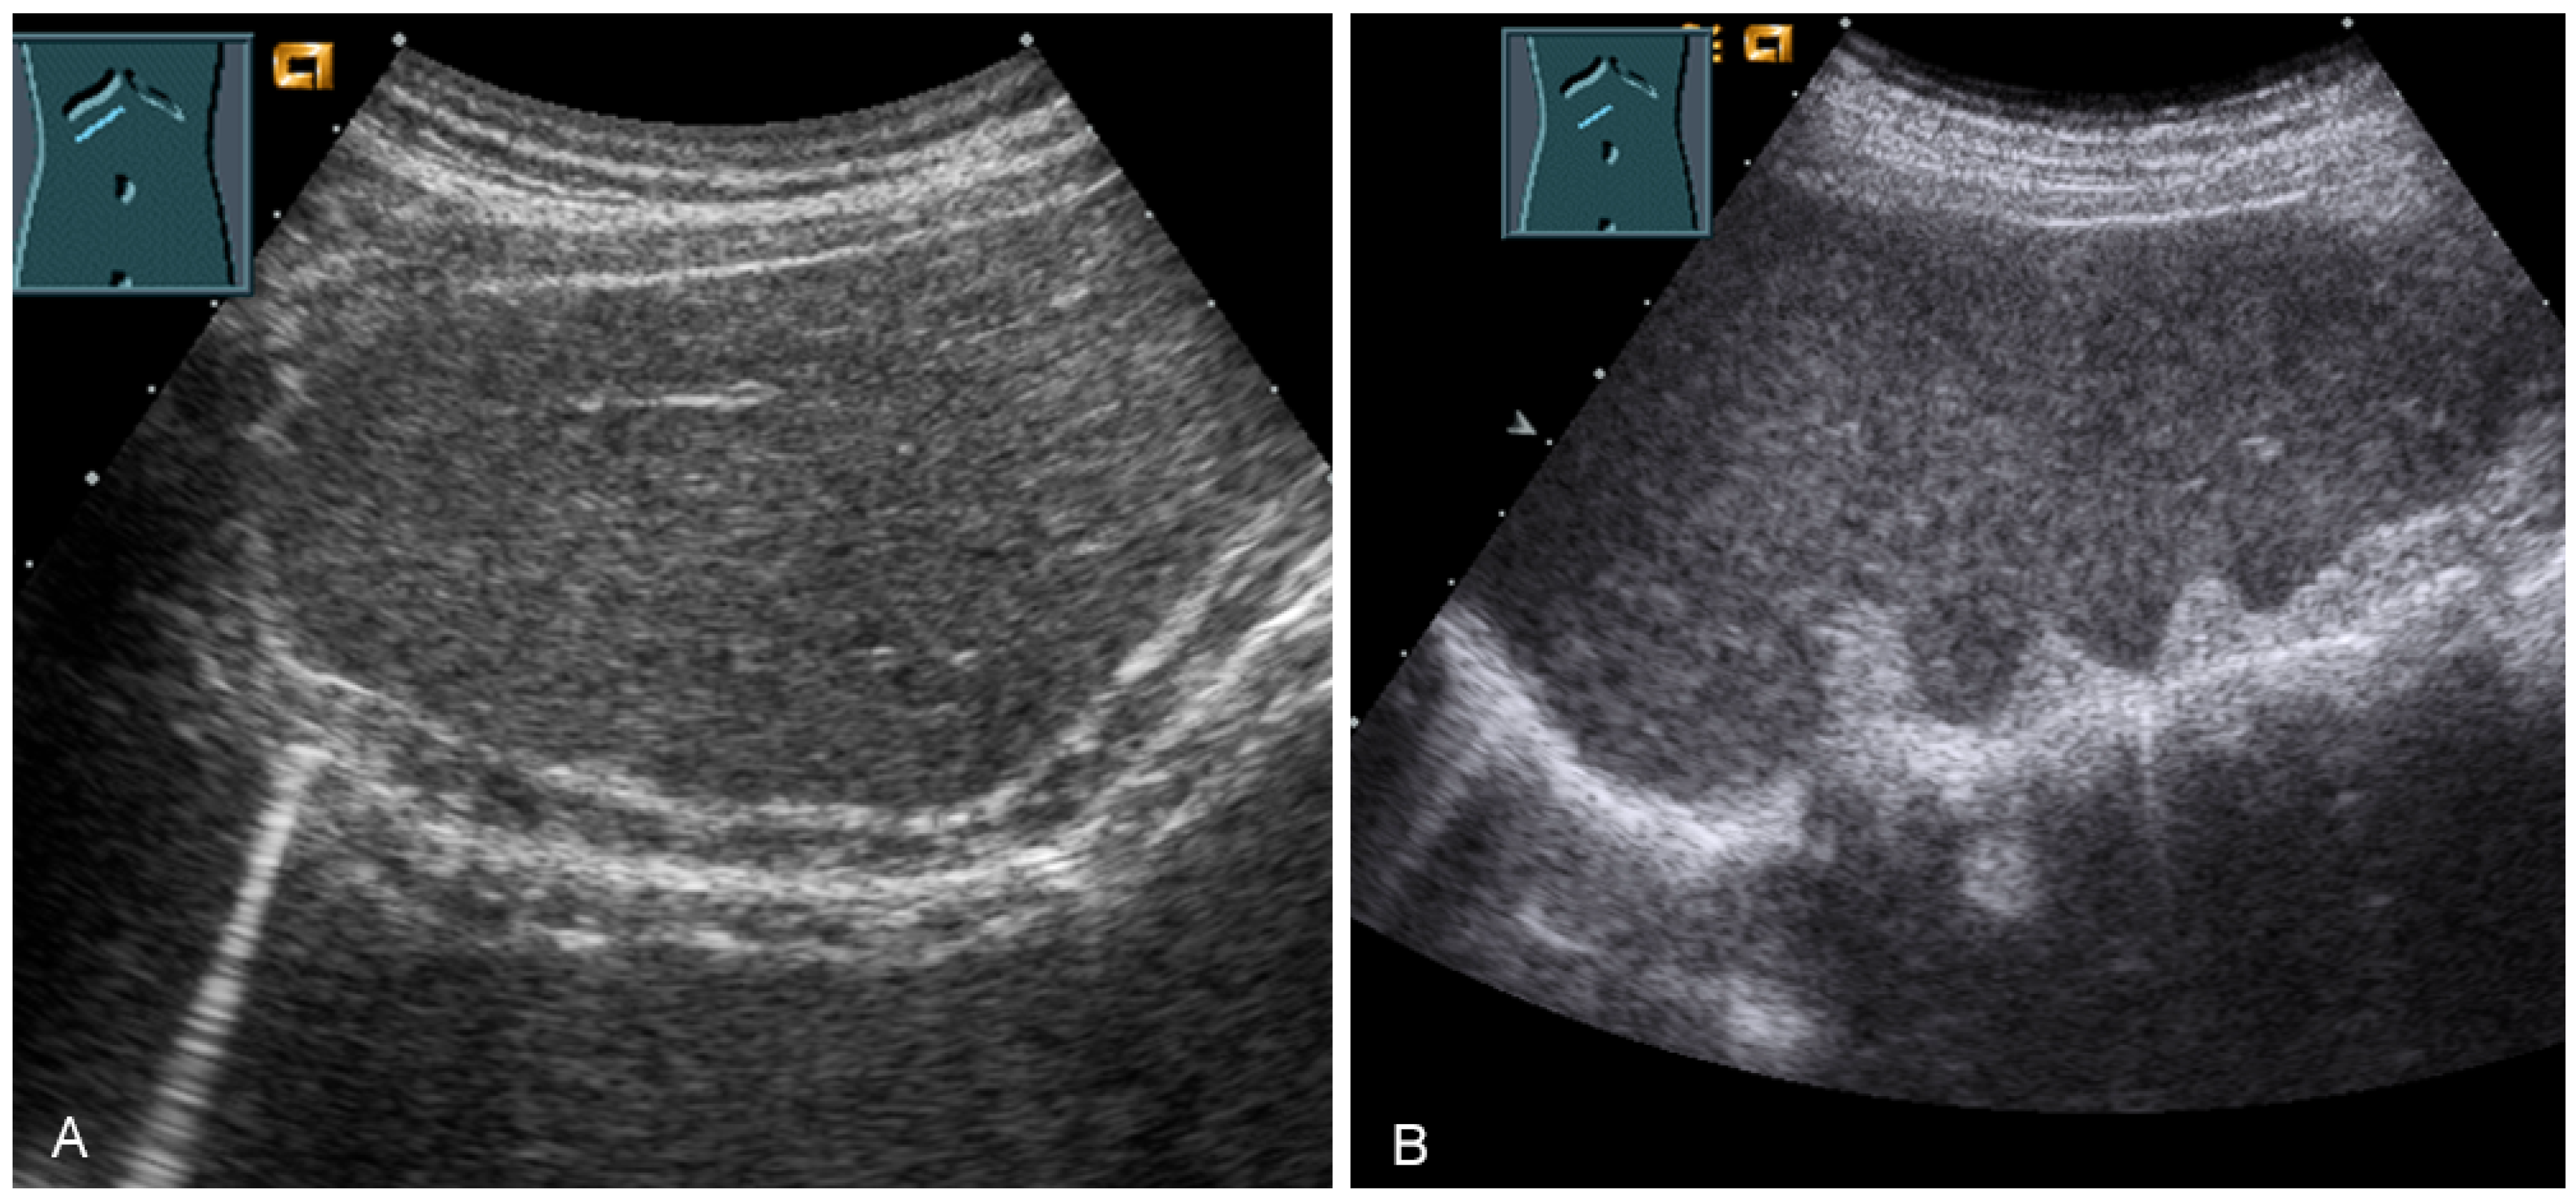

For sonographic evaluation of the diaphragm, the patient should be in the supine position with the head angled at 30°, as this position reduces examiner variability, increases reproducibility, and enhances excursion [52,53]. The supine position increases any paradoxical movement and at the same time limits any compensatory active expiration through the anterior abdominal wall that may mask paralysis [52]. From lateral intercostal approaches, the right diaphragm should be examined through the liver window and the left diaphragm through the spleen window (Figure 29) [53]. Limitations of left diaphragm visualization due to the small acoustic window can be reduced by adopting a more coronal view, parallel to the ribs. Pathologic conditions such as splenomegaly or hepatomegaly with a large left lobe facilitate the evaluation of the left diaphragm [52]. In addition, the right-sided diaphragm can be visualized in the subcostal transhepatic section with cranial tilt of the transducer (Figure 29).

Figure 29.

Visualization of the right-sided (A) and left-sided diaphragm (B) with the lateral intercostal view and of the right-sided diaphragm with the subcostal view (C).

Border shadow artifacts may indicate an apparent diaphragmatic gap, which disappears when the transducer position is changed (Figure 30).